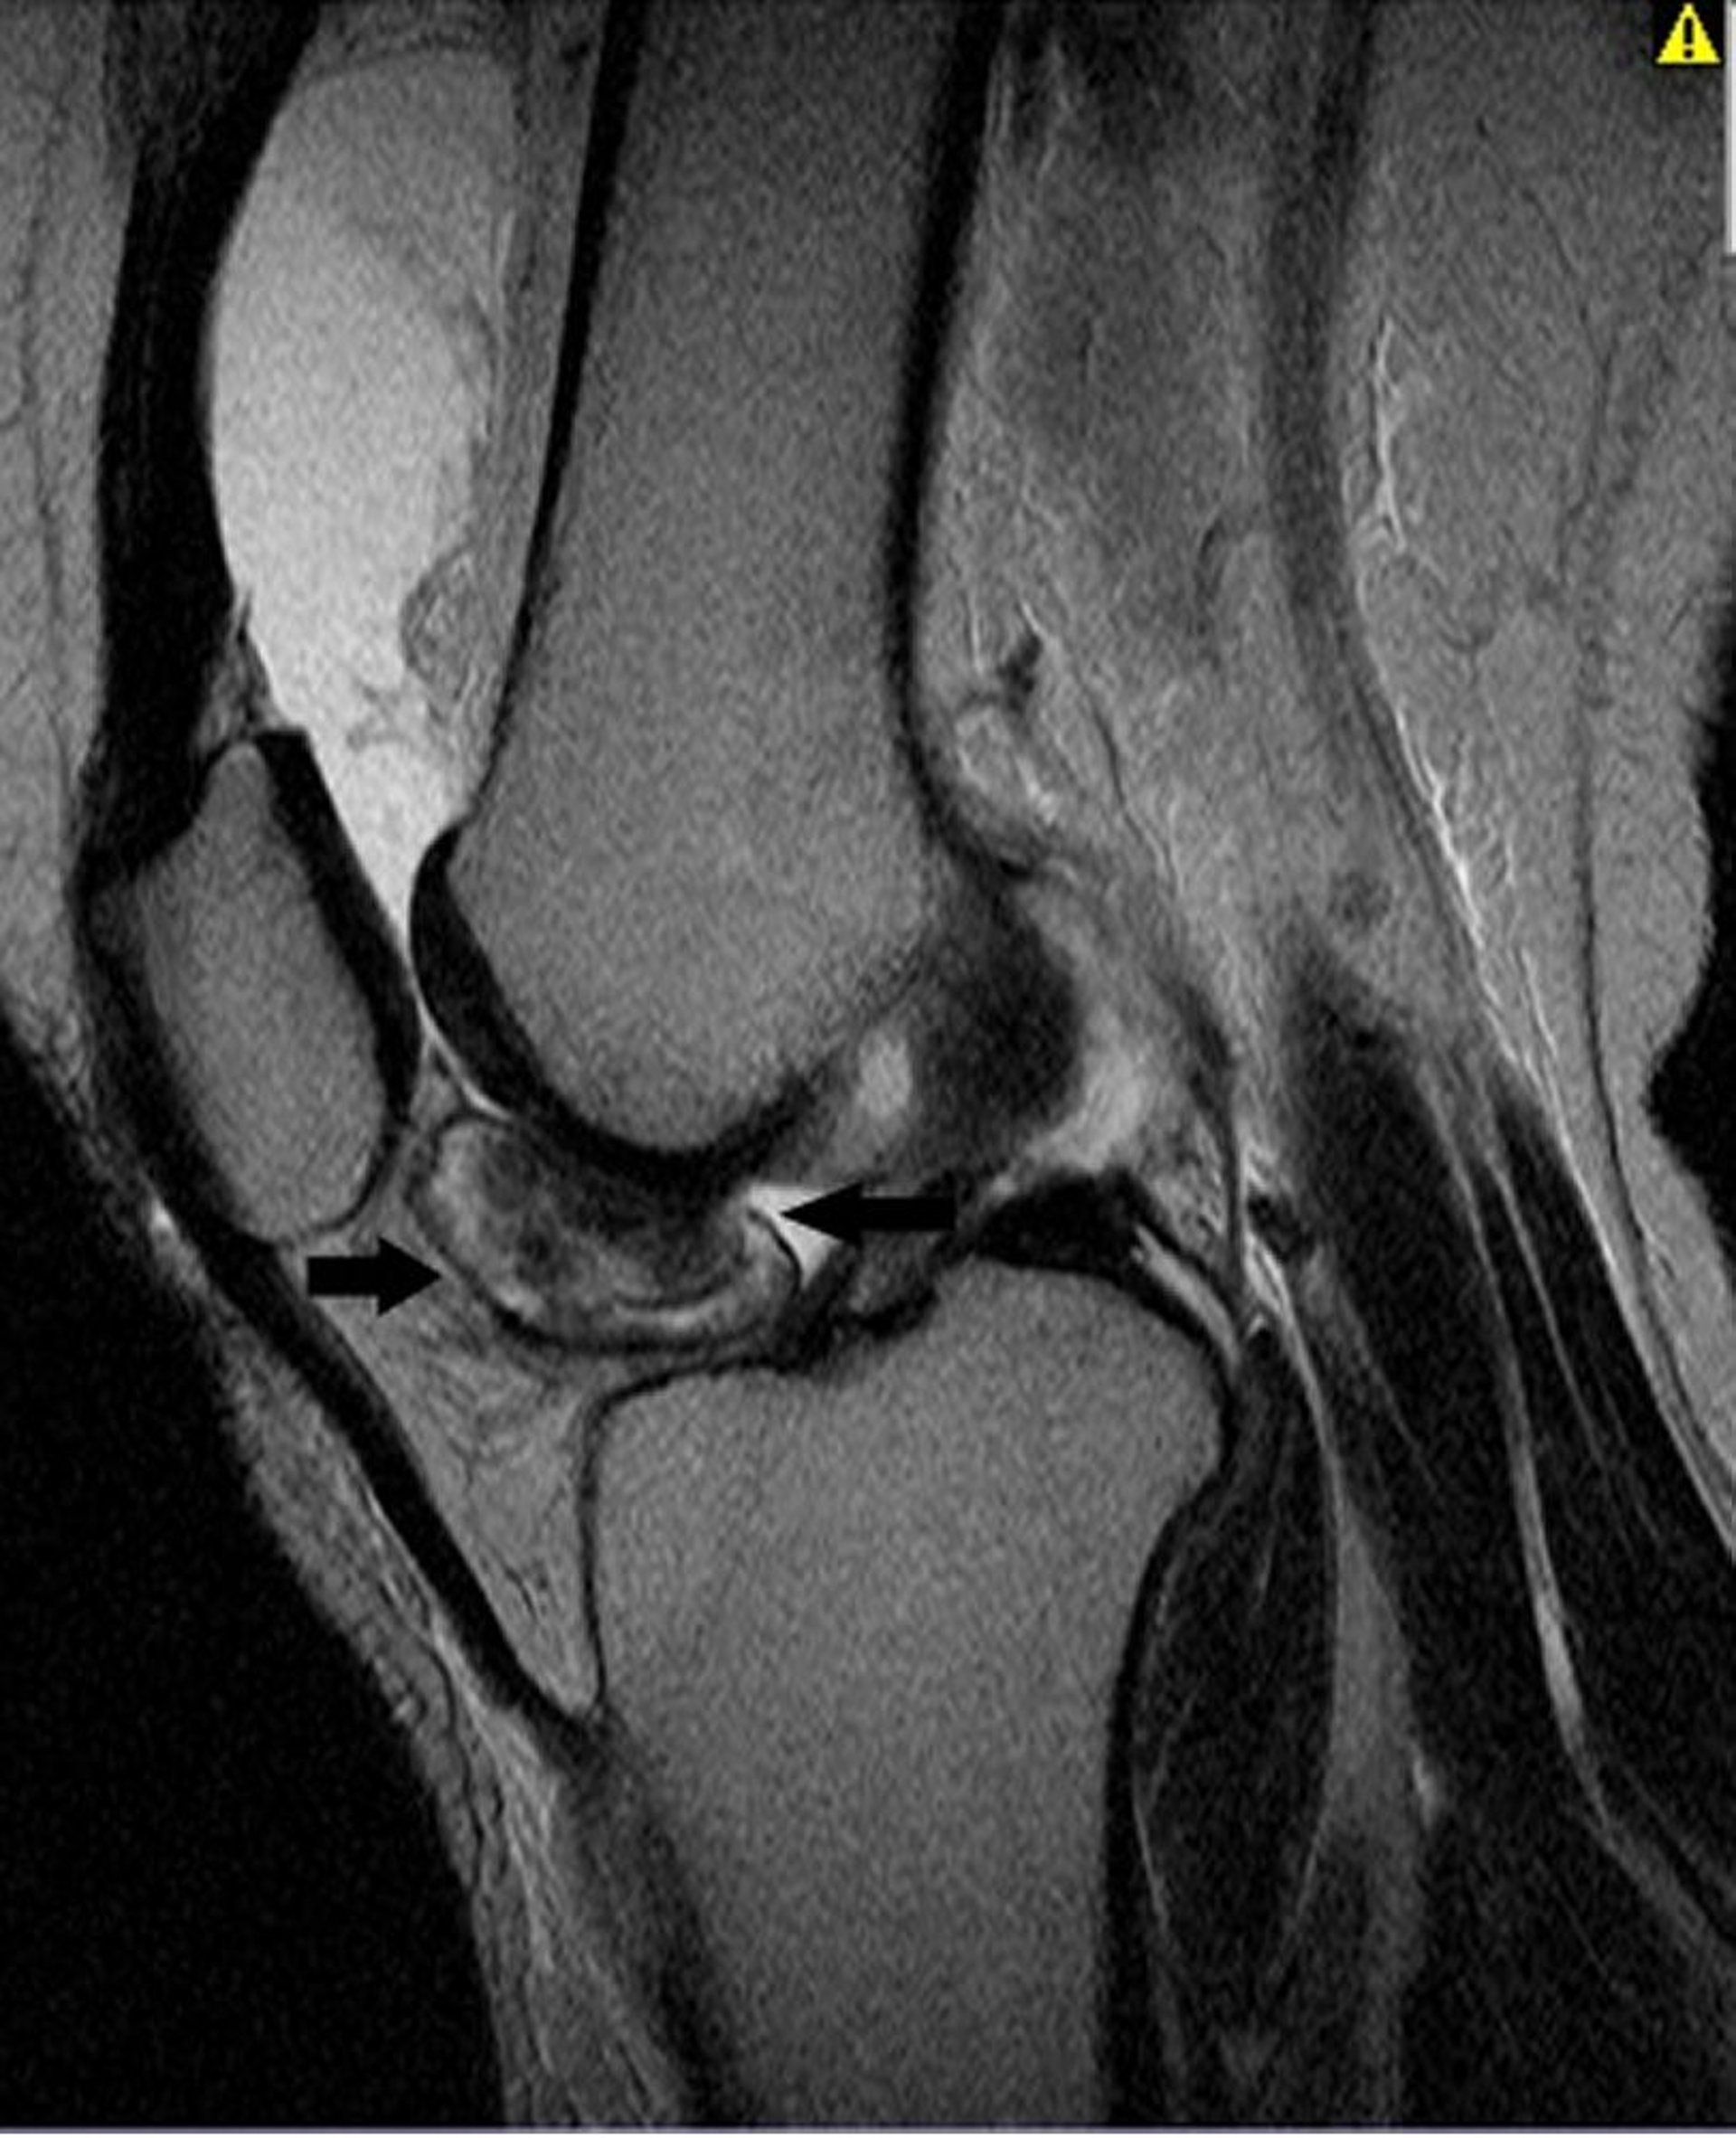

Questa RM del ginocchio mostra un tumore tenosinoviale a cellule giganti nel rivestimento dell'articolazione del ginocchio (frecce).

Image courtesy of Michael J. Joyce, MD, and Hakan Ilaslan, MD.